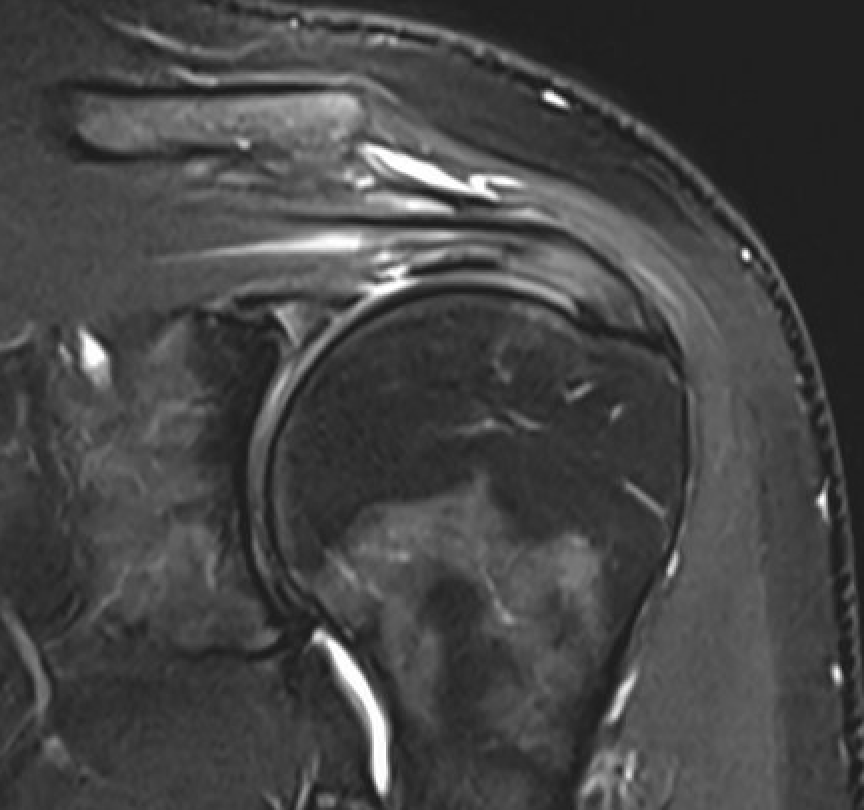

MRI

Inflammation and thickening of the rotator cuff tendons

Mild inflammation of the supraspinatus tendon insertion

Thickening and edema of the supraspinatus and infraspinatus tendon

Subscapularis tendinosis